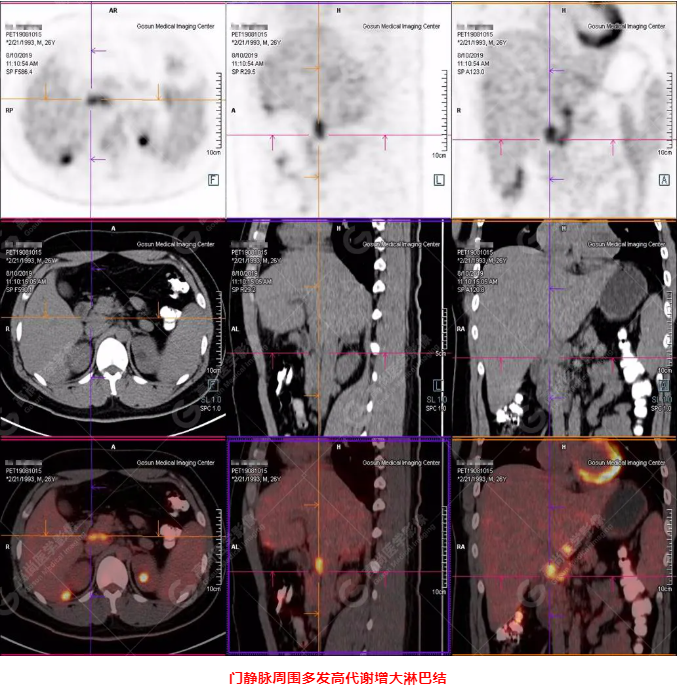

PET/CT全身圖

PET/CT診斷

嗜酸性粒細(xì)胞增多癥肝浸潤(rùn)

B超及CT檢查發(fā)現(xiàn):肝臟多發(fā)低密度占位。